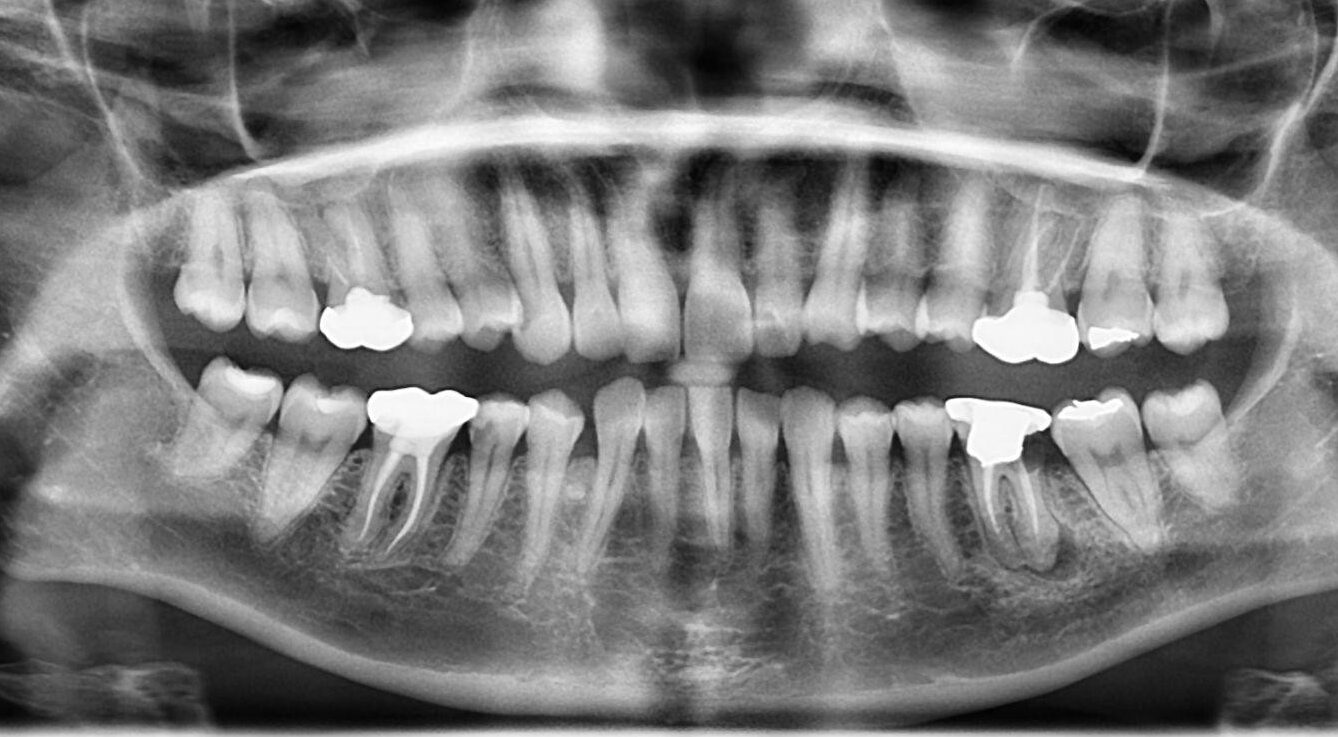

15. What option can be selected for following X ray?

16. What option can be selected for following X ray?

17. What options cannot be selected for this X ray?

18. What option can be selected for radiopacity in the tooth # 4.3 area?

19. What option can be selected for the following X ray?

20. Which option can be detected in this panoramic X ray?

21. Which option can be detected for this panoramic X ray?

22. What option cannot be detected in the following X ray?

23. What option cannot be selected for the following X ray?